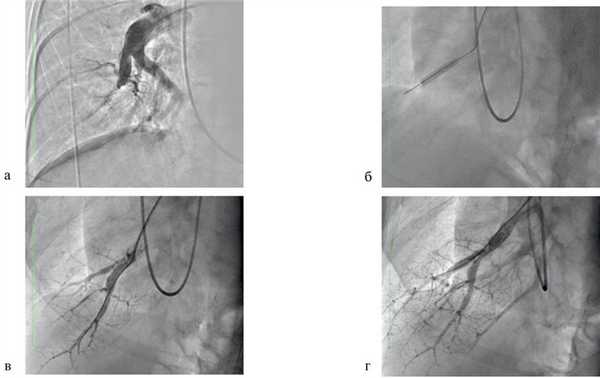

При МСКТ-ангиографии и инвазивной ангиопульмонографии диагностирован дистальный тип поражения ветвей ЛА, определены показания к медикаментозной терапии в сочетании с поэтапной БАПЛА. С учетом необходимости применения специфической терапии легочной гипертензии пациентке с высоким риском сердечно-сосудистых заболеваний для исключения ишемической болезни сердца выполнена коронарография: данных за стенозирующее поражение коронарных артерий не получено. На фоне терапии петлевыми диуретиками и силденафилом в дозе 60 мг/сут достигнута компенсация сердечной недостаточности на уровне III функционального класса с купированием отечного синдрома. Под контролем рентгеноскопии и инвазивного мониторинга параметров центральной гемодинамики был выполнен первый этап баллонной ангиопластики хронической окклюзии устьев сегментарных артерий А8, А9 правого легкого. Использован баллонный катетер высокого давления диаметром 5,0 мм, длиной 20,0 мм (максимальное давление инфляции — 12 атм.). Восстановлен антеградный кровоток с появлением венозной фазы (скорость кровотока PFG — 3 балла) (рис. 2). Рис. 2. Баллонная ангиопластика хронической окклюзии сегментарной артерии А8 правой ЛА. а — окклюзия сегментарной ветви А8; б — проведение коронарного проводника через область окклюзии на периферию артерии с последующей дилатацией баллонным катетером; в — восстановление кровотока по артерии; г — баллонная пластика ветви второго порядка сегментарной артерии А8. Расчетный индекс PEPSI — 58,5; риск развития реперфузионного отека легкого — около 80%. Интраоперационное давление в ЛА на момент завершения процедуры составило 85/32/53 мм рт.ст., системное артериальное давление — 136/81 мм рт.ст.